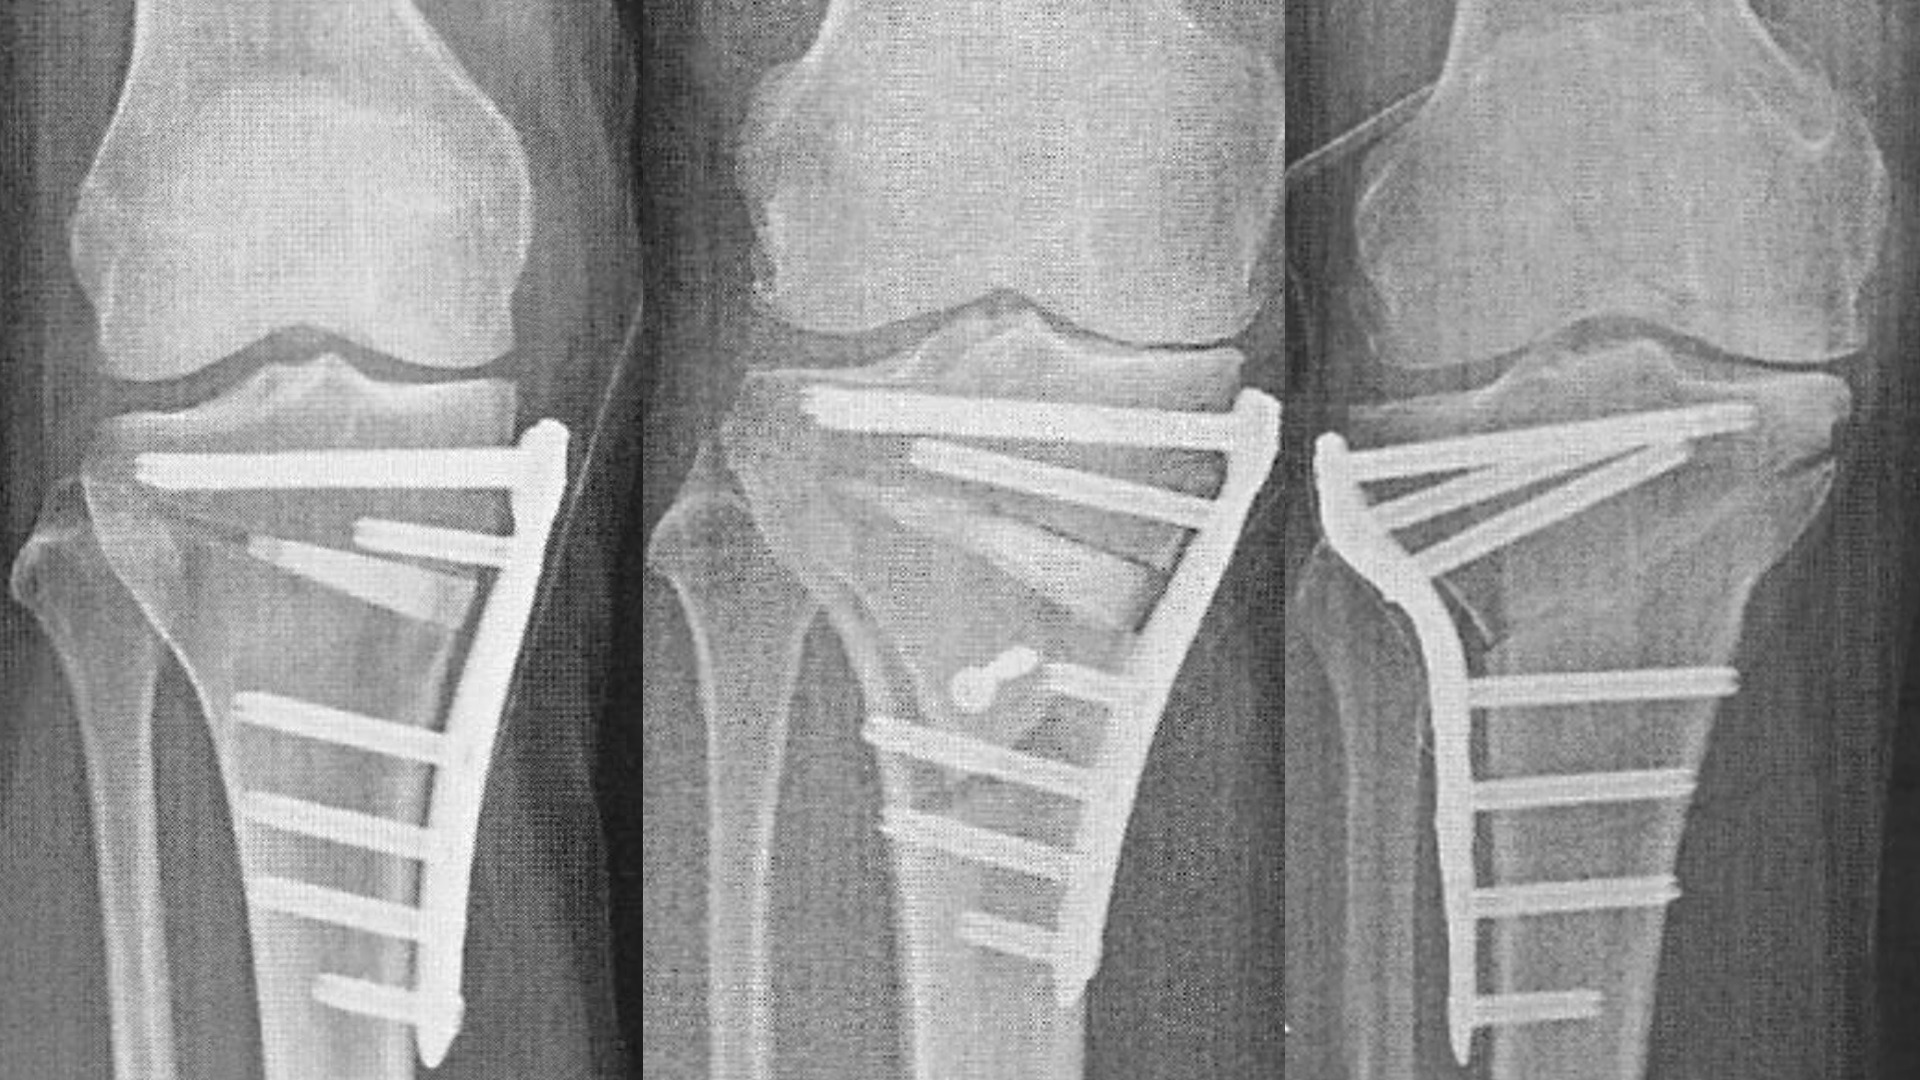

膝関節外科

高位脛骨骨切り術(HTO)

変形性膝関節症(OA) 定義 関節軟骨の欠損を生じ,関節周辺の骨組織に変化をきたした結果,...